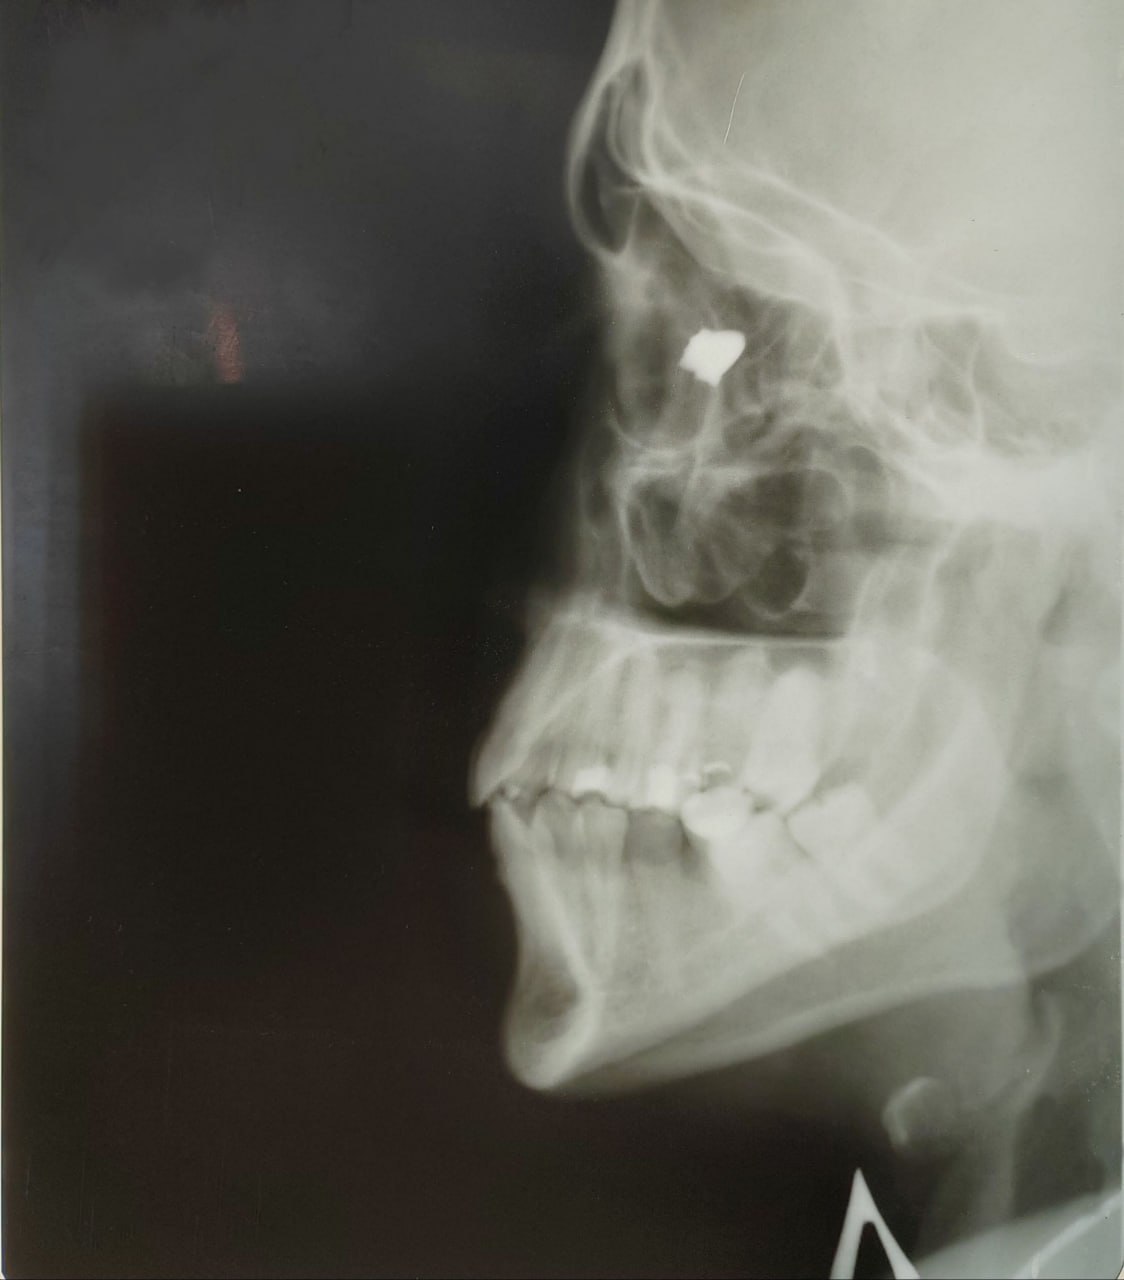

У пациента диагностировали серьезное проникающее ранение склеры, сопровождавшееся выпадением стекловидного тела и кровоизлиянием в глаз, известным как гемофтальм. Дополнительно зафиксирована травматическая отслойка сетчатки, повреждение глазодвигательной мышцы и рана века. Зрительная функция глаза практически утеряна. По словам врача Петра Чернядьева при поступлении глаз был похож на пустой шарик, а зрение снизилось до 1 процента. Проведена рентгенография для определения местоположения инородного тела и спланирована операция.